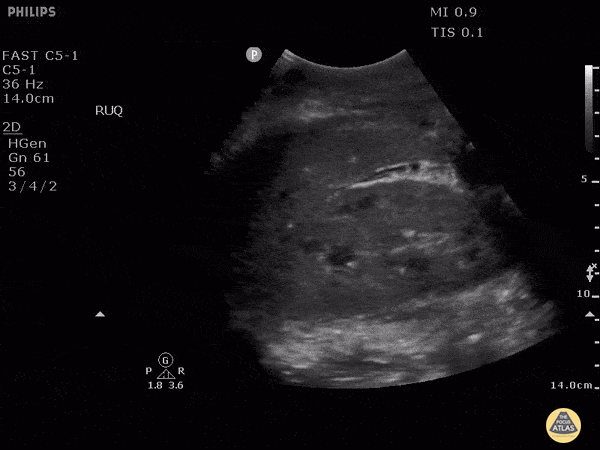

This is RUQ view from a patient who presented to the emergency department after falling from a roof and with low blood pressures. Although there appears to be perihepatic fluid, an interesting learning point form this case is whether or not we can discern if fluid observed is truly in the retroperotineal space or in the peritoneal cavity. Because the fluid is in direct contact with perinephric fat, this is actually in the retroperitoneal space and not in the peritoneal cavity. This may be difficult to distinguish in patients with very little perinephric fat. Image courtesy of Robert Jones DO, FACEP @RJonesSonoEM Director, Emergency Ultrasound; MetroHealth Medical Center; Professor, Case Western Reserve Medical School, Cleveland, OH View his original post here